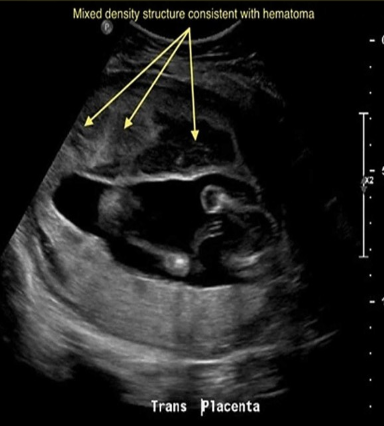

chorioangioma is supected. which image shows it

a) A

b) B

c) C

d) D